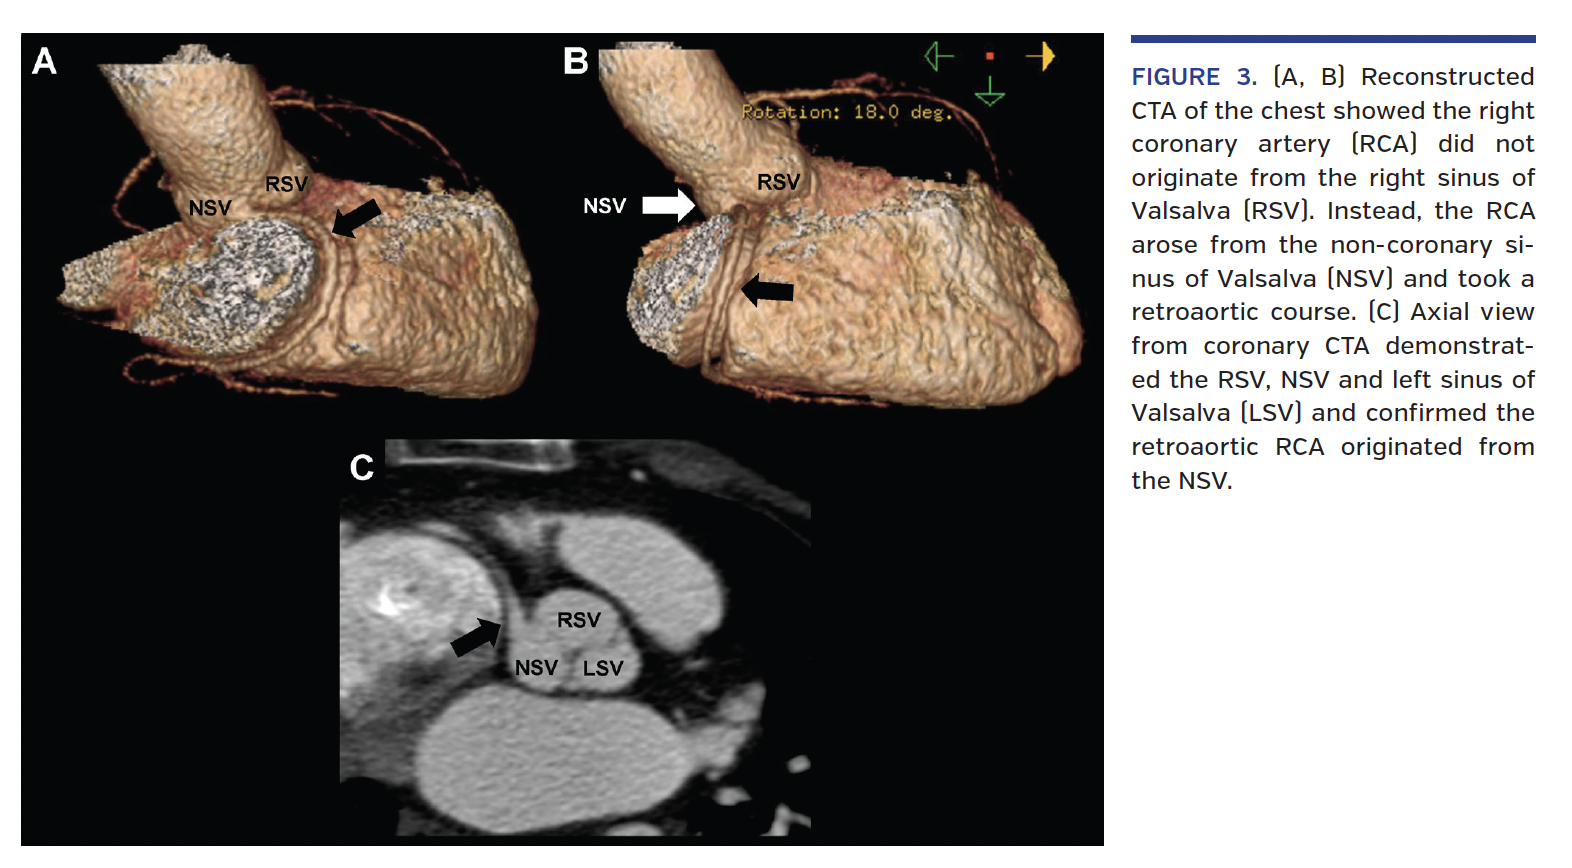

Case 3. A 66-year-old woman presented with recurrent atrial flutter and fibrillation for consideration of an ablation. Preablation chest CTA was performed to evaluate the pulmonary veins. This demonstrated an anomalous RCA originating from the NSV (Figures 3A-3C). To our knowledge, this is the first ever reported case of this anomaly.